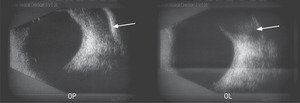

W badaniu ultrasonograficznym oczodołów wykazano nieregularne hipoechogenne struktury w rzucie obu gruczołów łzowych, powodujące ich powiększenie (ryc. 3).